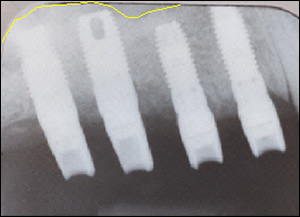

Fig 3: Using the Summer's Technique the floor of the maxillary sinus was gently elevated to accomodate four dental implants.

Fig 4: The repositioned sinus floor.